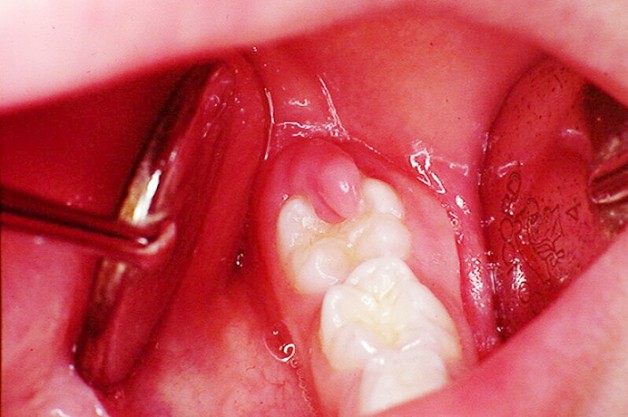

Viêm lợi trùm là tình trạng mô nướu bị viêm hoặc sưng tấy che phủ lên trên bề mặt của răng. Tình trạng này phổ biến hơn ở răng hàm dưới và thường xảy ra xung quanh răng khôn. Hầu hết người mắc phải tình trạng lợi trùm răng là ở cuối tuổi thiếu niên hoặc đầu những năm 20 tuổi.

Khi xem hình ảnh bị viêm lợi trùm là phần lợi bao phủ trên bề mặt răng. Lợi trùm có thể phủ kín hoặc phủ một phần răng. Bình thường, khi răng mọc phần lợi này sẽ dần tiêu biến. Tuy nhiên, một số trường hợp phần lợi trùm này sẽ che phù và cản trở sự phát triển của răng gây đau đớn. Về lâu dài khi răng mọc lên, đẩy một phần lợi trùm tạo nên khoảng trống dưới lợi. Trong trường hợp này, nếu không chăm sóc và vệ sinh răng miệng cẩn thận, rất có thể lợi sẽ viêm và sưng.

Viêm lợi trùm răng khôn có thể hình thành khi răng khôn chỉ nhú 1 phần (đâm thủng nướu). Sự phát triển mô mềm trên chiếc răng khôn đã mọc 1 phần được gọi là túi lợi, tạo điều kiện cho vi khuẩn trú ngụ, tăng sinh và gây bệnh nhiễm trùng, sưng tấy tại chỗ rồi sẽ lan rộng sau đó.

viêm lợi trùm

Hình ảnh viêm lợi trùm lên răng gây đau nhức